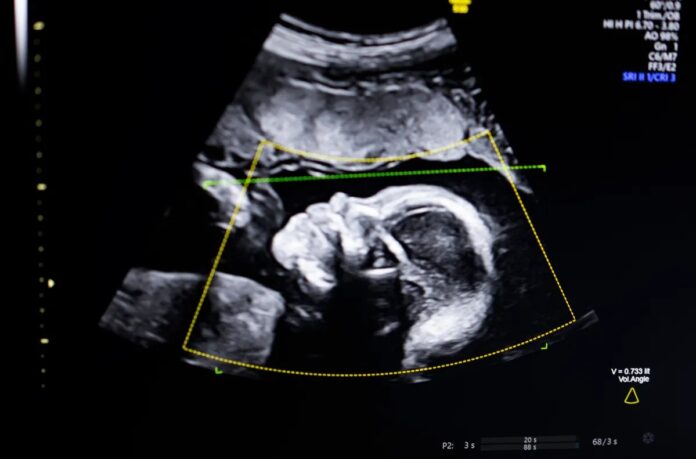

Пренатальне ультразвукове дослідження є ключовим методом спостереження за вагітністю, але якість зображення дуже різна. Погана чіткість зображення може призвести до неправильного діагнозу, ризик, який непропорційно впливає на вразливі групи населення, включно з темношкірими жінками, у яких рівень материнської смертності значно вищий. Сполучені Штати мають одні з найгірших показників здоров’я матерів серед усіх розвинених країн, і цей інструмент має на меті допомогти це покращити.

Програмне забезпечення використовує комп’ютерне бачення на основі штучного інтелекту для підвищення точності ультразвукових оцінок кількома способами:

- Оцінка якості: автоматично перевіряє чіткість зображення.

- Перевірка повноти: підтверджує, що всі ключові анатомічні структури видимі.